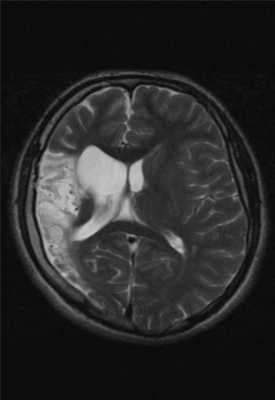

Внутримозговая гематома (граница острой и ранней подострой стадий - 3 суток), осложнившаяся внутрижелудочковым кровоизлиянием.

Внутримозговая гематома, поздний подострый период (14-21 день) с перифокальным отеком вокруг гематомы.

Внутримозговая гематома правой теменной доли. Граница поздней подострой и ранней хронической стадии. В Т2-ВИ виден ободок гемосидерина (стрелка).

Хочется подчеркнуть возможность МРТ в выявлении последствий геморрагического поражения - остается хорошо дифференцируемый по Т2 ободок гемосидерина, недоступный для визуализации при других методах нейровизуализации.

Стрелками показан ободок гемосидерина по периферии постишемической кисты.